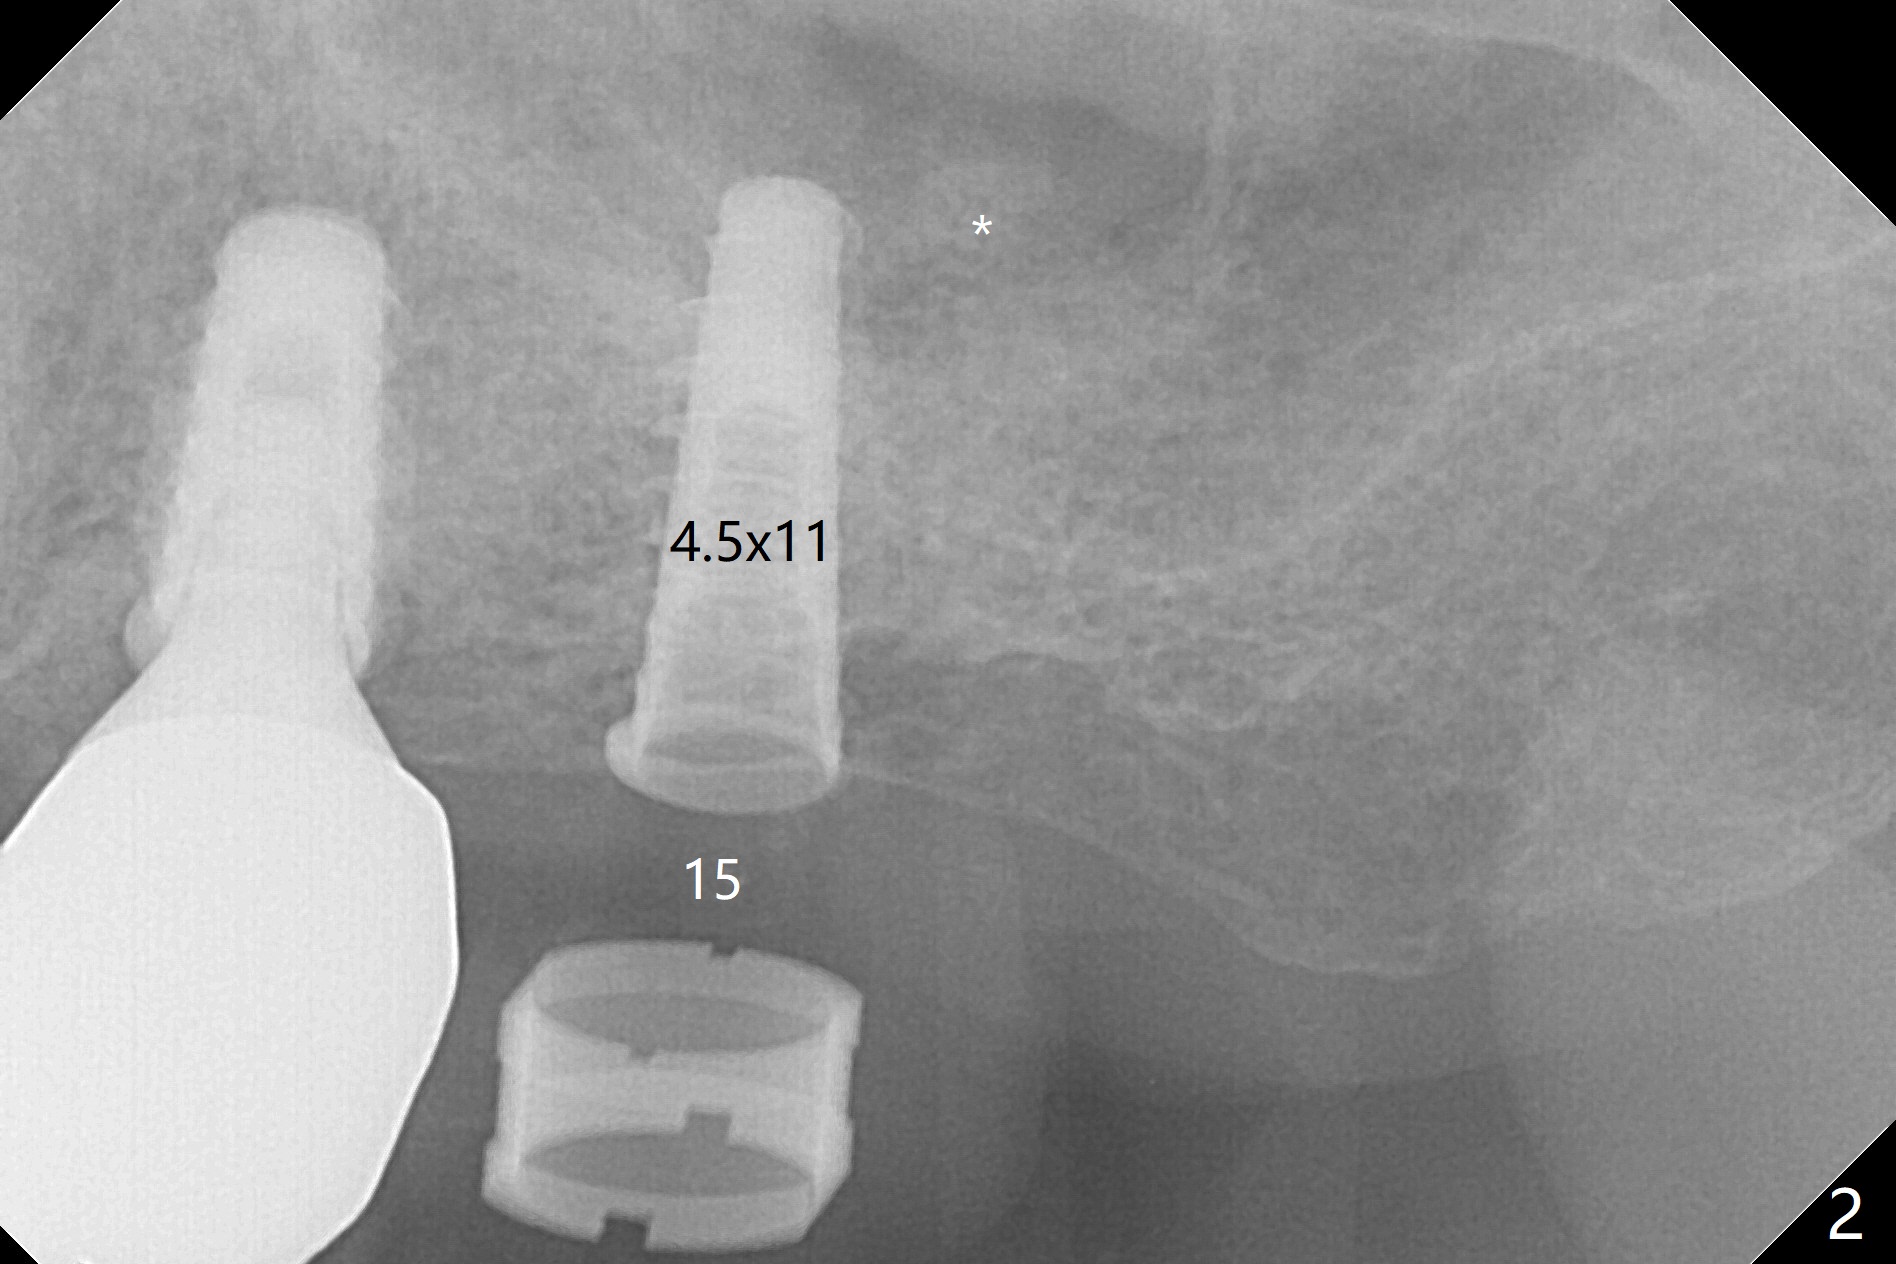

After finishing osteotomy with IS guide and Tatum Tapered tap 5x14 mm for 11 mm (gingival level) free hand, a 5x11 mm Tatum implant is placed at #18 with >15 Ncm (Fig.1). Bone harvested from the site of #18 will be used for #15 sinus lift (Fig.2 * as well as allograft). By the similar fashion, osteotomy at #15 is finished according to IS drill sequence except underdrilling (4.0x7.3 mm drill with 2 O-rings). Following use of DIO Sinus Approach Kit and placement of 2 pieces of PRF membrane and mixture of autogenous and allograft for sinus lift, a 4.5x11 mm IBS dummy implant is placed (Fig.2). With more allograft for sinus lift, a 5x9 mm implant is inserted with >35 Ncm (Fig.3). At #18 the implant 2.5 months postop (Fig.4) seems ok with removal of the cover screw and placement of a healing cuff. The implant at #15 appears osteointegrated with sinus lift 2.5 months postop (Fig.5 *). Half month later, the implant at #18 is tender associated with unipost placement. The healing abutment returns. A pair abutment (5.5x4(4) mm; 25 Ncm) is placed at #15. When the patient returns 7 months postop, BWs are taken to confirm that the abutment at #15 is fully seated, whereas that at #14 is not (Fig.6). A healing abutment is then placed at #14. Osteointegration seems to occur at #18; there is no tenderness when a 4.5x3 mm abutment is placed (Fig.7). Provisional crowns are fabricated at #15 and 18 for progressive loading. When the patient returns 14 months postop, a 5x4(4) mm hex abutment is placed at #14 with apparent gap between the implant and abutment (Fig.8 (PA) open arrow). In fact the gap seems to be absent more coronally as shown by bitewings (Fig.9,10 <). All of the 3 crowns are cemented in situ (Fig.11, 12) although the one at #14 is removed with the abutment for removal of residual cement. When the latter is re-torqued, the abutment remains completely seated (Fig.12). However, the implants at #15 and 18 appear to be placed distally with free-end guides (black lines).